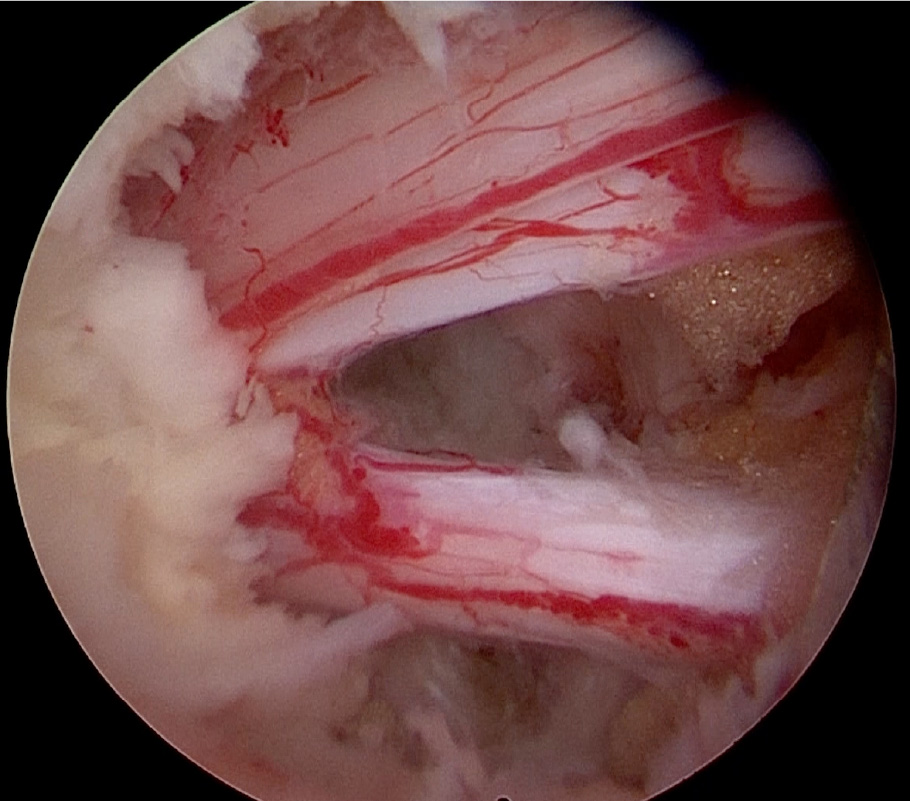

術中写真:

【第4/5腰椎部腰部脊柱管狭窄症に対する2双式内視鏡下椎弓切除(aFESS)の実例】

術前MRI:靱帯や骨が厚く変性し、

神経の通り道(脊柱管)が狭くなっています(丸印)。